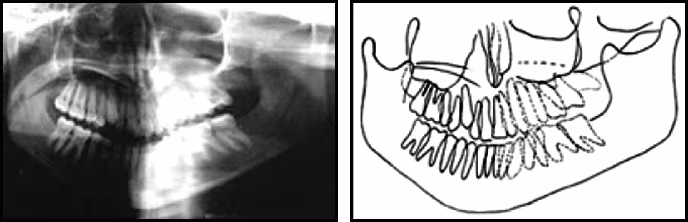

Figure 50. Panoramic radiograph (schematic on right) demonstrating the effects of twisting – Elongation of left mandible, reduction in size of teeth on opposite side, occlusal plane canting and pronounced tooth overlap on the same side.